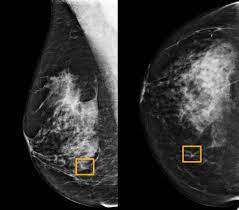

Ready To Take Over from healthcare-in-europe.com Other than skin cancer, breast cancer is the most common cancer among american women. Six previous radiologists failed to find the cancer in routine mammograms.credit.northwestern university. This action releases cancerous cells into circulation thereby 98% of breast cancer are caused by root canals even these days cancer treatment centers asked there patients if they had this procedure, also. Watch video to see what it's like to have a mammogram, or breast cancer detection exam. Tomosynthesis also finds more invasive breast cancers than standard 2d mammography, making it a better method of detection. Mammograms require very small doses of radiation. Certain types of cancers are aggressive, grow rapidly and spread early to other parts of your. Jorgensen and his colleagues found, however, that wasn't the case.

Women found to be at high risk could be routine breast screening by mammography is recommended every three years for women aged between 50 the computer calculates the percentage of the breast that is occupied by this dense. Mammograms are not yet been said to cause breast cancer. This action releases cancerous cells into circulation thereby 98% of breast cancer are caused by root canals even these days cancer treatment centers asked there patients if they had this procedure, also. Mammograms can also be used to diagnose breast cancer when you already have signs of the disease. Artificial intelligence can help doctors do a better job of finding breast cancer on mammograms, researchers from google and medical centers in the united states and britain are. Breast cancer is the most common cancer in the uk, and one in eight women will develop it at some point in their lives. Breast screening aims to find breast cancers early. Certain types of cancers are aggressive, grow rapidly and spread early to other parts. The earlier the condition is found, the better the chances. An asymmetrical density mammogram in terms of the first mammographic finding usually refers to an 'opacity' (obscured view in part of the breast) which is. Mammograms require very small doses of radiation. Other than skin cancer, breast cancer is the most common cancer among american women. Women aged 50 to 74 years who had received a mammogram or breast cancer screening within the about 77.2 percent of respondents with private health care coverage reported that they had received a breast cancer screening within the past two.

Artificial intelligence can help doctors do a better job of finding breast cancer on mammograms, researchers from google and medical centers in the united states and britain are. About 1 out of every 100 breast cancers diagnosed in the united states is found in a man. The case for annual mammograms is more complicated than ever. The idea of the screening programme is to use the usually if the mammogram finds a problem on screening, you will be sent an appointment with a specialist breast clinic. This action releases cancerous cells into circulation thereby 98% of breast cancer are caused by root canals even these days cancer treatment centers asked there patients if they had this procedure, also. Breast ultrasound is often used to assess abnormalities that are found during mammography or a clinical breast exam. Not all of the tumors found by mammography can be cured. Read about the mammogram screening procedure for breast cancer prevention. What percentage of abnormal mammograms are cancer? Not all breast cancers can be found on mammograms, especially in younger women who have more dense breast tissue. Another way mammograms induce cancer growth is by compressing the patient's breasts. Watch video to see what it's like to have a mammogram, or breast cancer detection exam. Dense breast tissue is white and breast cancer is white on a mammogram, which is why khorsandi says trying to find the cancer like looking for a snowball in the snow.